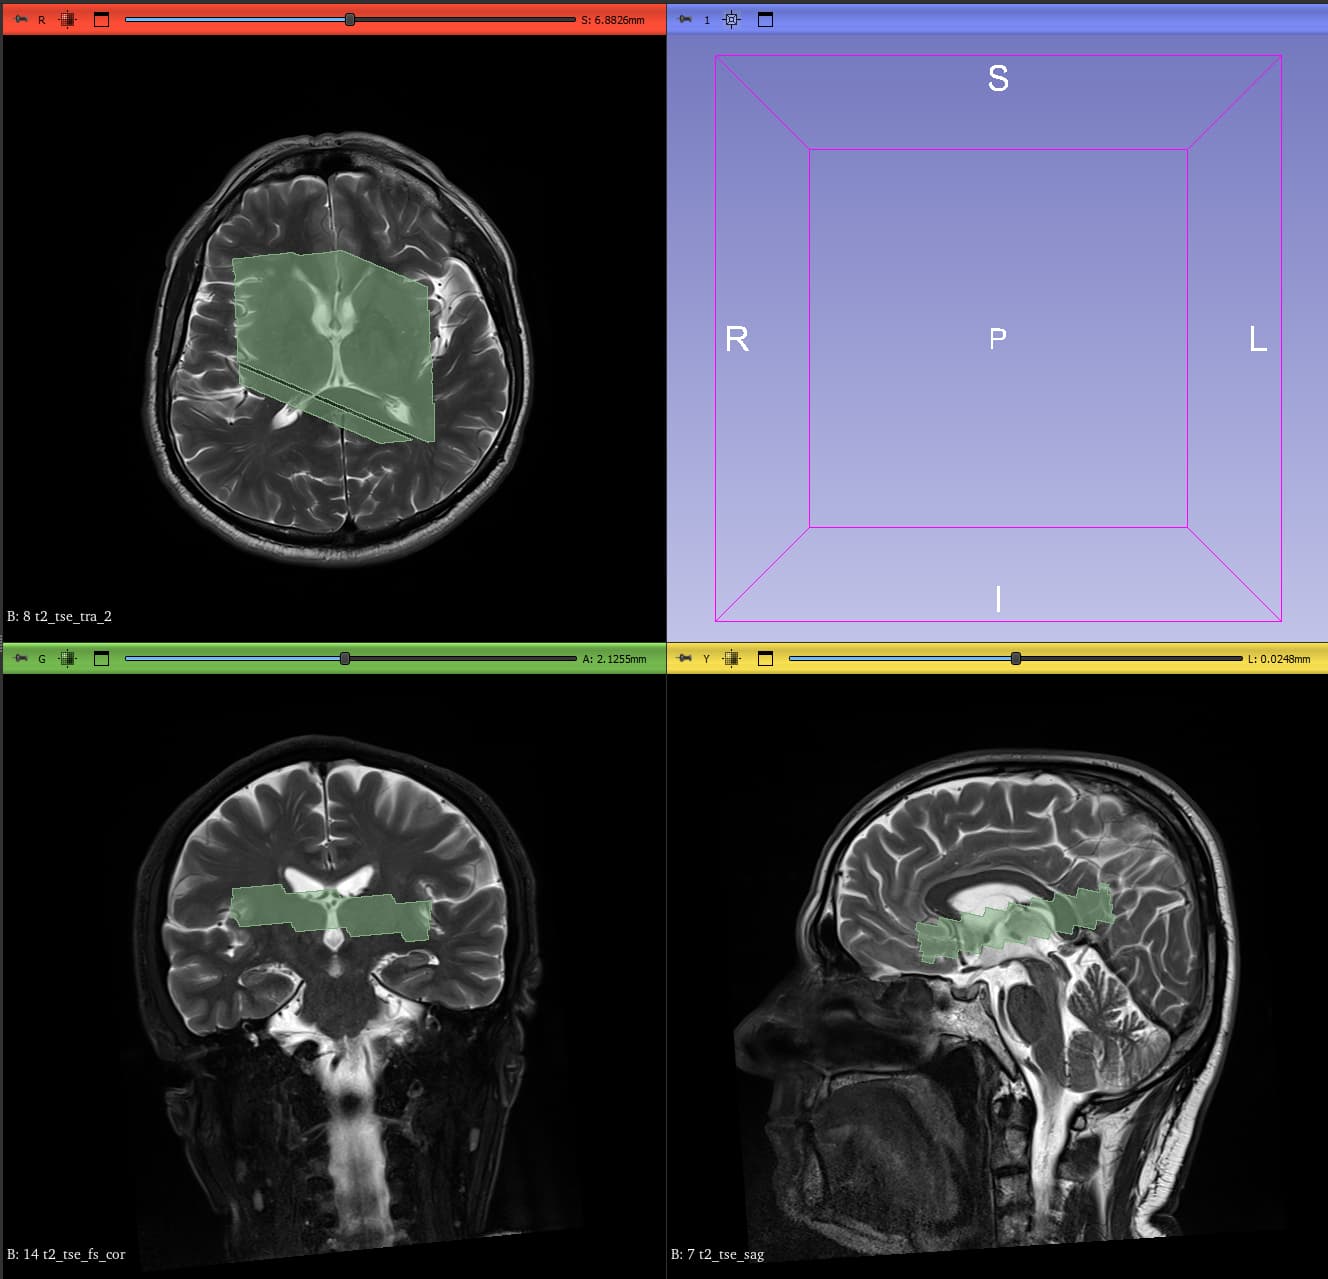

I am currently working on Siemens .rda data acquired on an XA20 system and I am trying to generate voxel masks. I have been struggling with this for a while, and because of an issue I encountered, I opened this thread where @mmikkel kindly tried to help. After re-examining both the code and the generated masks, I realized that although the voxel position is correct, the orientation is inverted in all directions (can be seen when comparing the scanner image with the generated voxel mask bellow). Initially, I thought the problem was limited to the axial plane, but it turns out that all orientations are flipped.

I tried changing the signs of the angle-related parameters (SlabOrientation) and experimented with different ways of generating the masks. I also tested the codes of several different software packages (Gannet, Osprey, FID-A, rda2nifti), but none of these approaches solved the problem. In every case, the voxel masks are produced with a mirrored or inverted orientation.

I used your code since @meggon’s data and mine share the same headers. It generated the voxel box correctly (except that I replaced PositionVector with the MidSlabPosition values), but the orientations were inverted, as shown in the screenshots above.